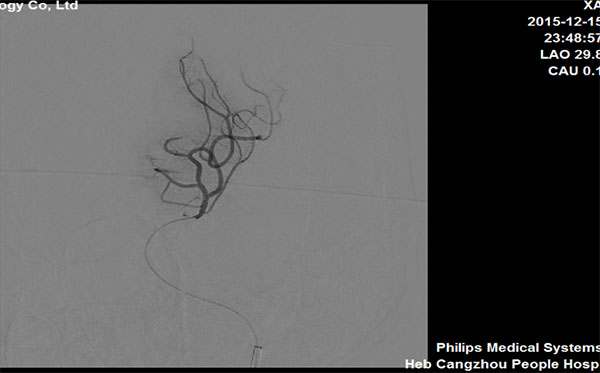

手术首次取栓

图3

图4